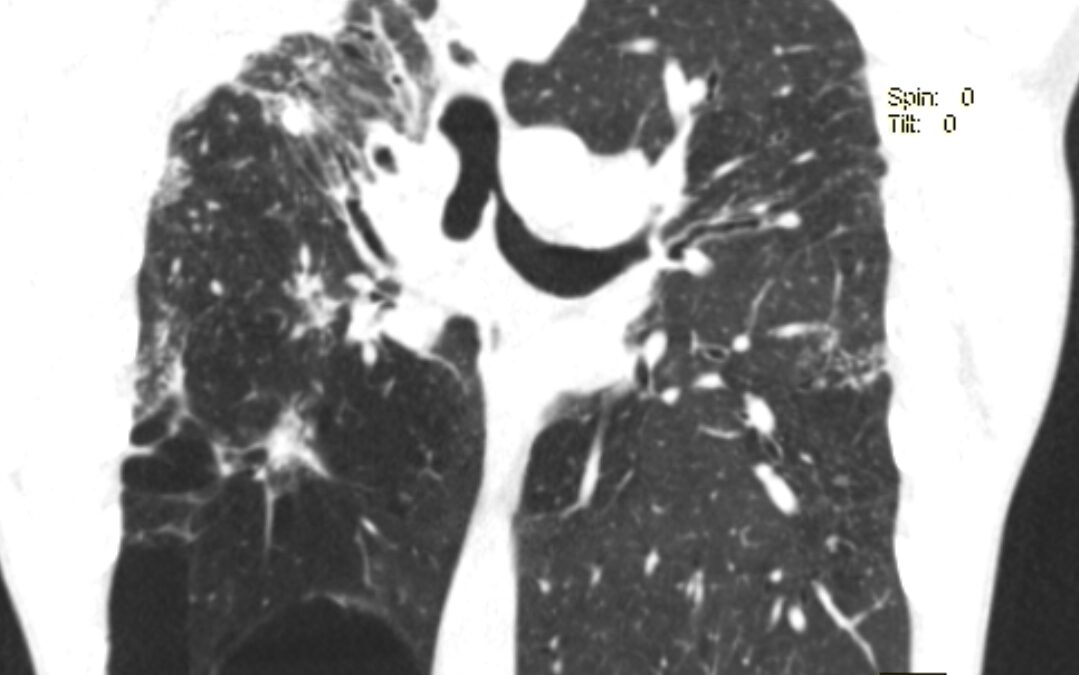

ფილტვის მოცულობის ბრონქოსკოპიული შემცირება ბულოზური ემფიზემის შემთხვევაში პაციენტი 42 წ მამაკაცი. აქტიური მწეველი. თავს ავად გრძნობს რამოდენიმე თვეა. ჩივილები: ძლიერი ქოშინი ფიზიკურ დატვირთვაზე, ჰაერის უკმარისობა, საერთო სისუსტე. გულმკერდის კტ კვლევით – ორივე...